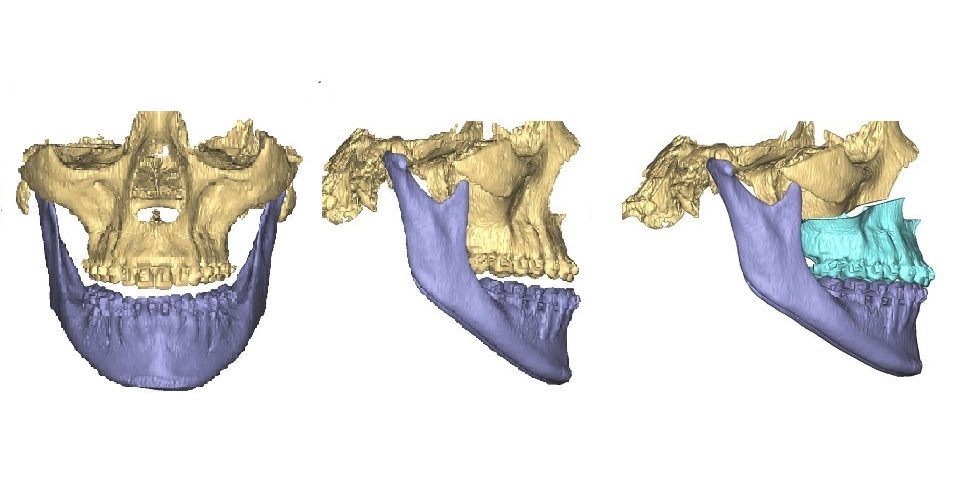

Dr. Limchayseng’s practice covers all the diagnostic, surgical and rehabilitative procedures to treat injuries, diseases and defects of the mouth, oral cavity, jaw and facial areas. We diagnose and manage skeletal-facial deformities, obstructive sleep apnea, surgical placement of dental implants and bone grafting, removal of impacted wisdom teeth, cyst and tumors of the jaws and traumatic injuries to the soft and hard tissues of the head and neck. We provide surgical care for patients of all ages. We take special pride in taking care of children by providing them with a safe environment, atraumatic care because of Dr. Limchayseng’s expertise in the management of pediatric oral surgery patients. For the convenience of our patients, we have two state of the art practice locations.